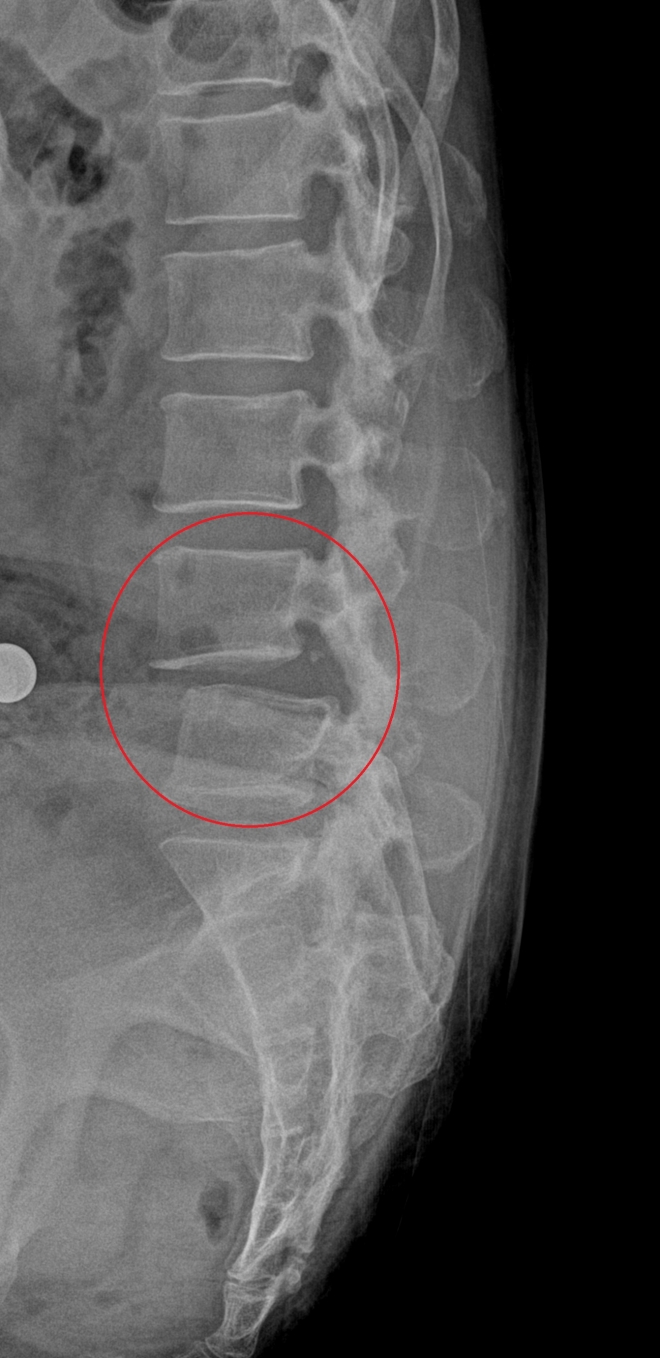

진단은 비교적 간단해 X선 검사만으로 척추 뼈의 어긋난 정도를 쉽게 확인할 수 있다. 문제는 증상이 미미한 초기 단계일 경우 누워서 X선을 찍으면 확인이 어렵다는 점. 앞뒤로 밀려 나온 정도를 확인하기 위해서도 반드시 서 있는 상태와 앞으로 숙여서 X선 촬영을 해야 정확하게 진단할 수 있다. 다리 저림이 심하고, 척추관협착증 동반이 의심될 때는 자기공명영상(MRI) 촬영을 통해 정밀하게 상태를 확인하기도 한다.